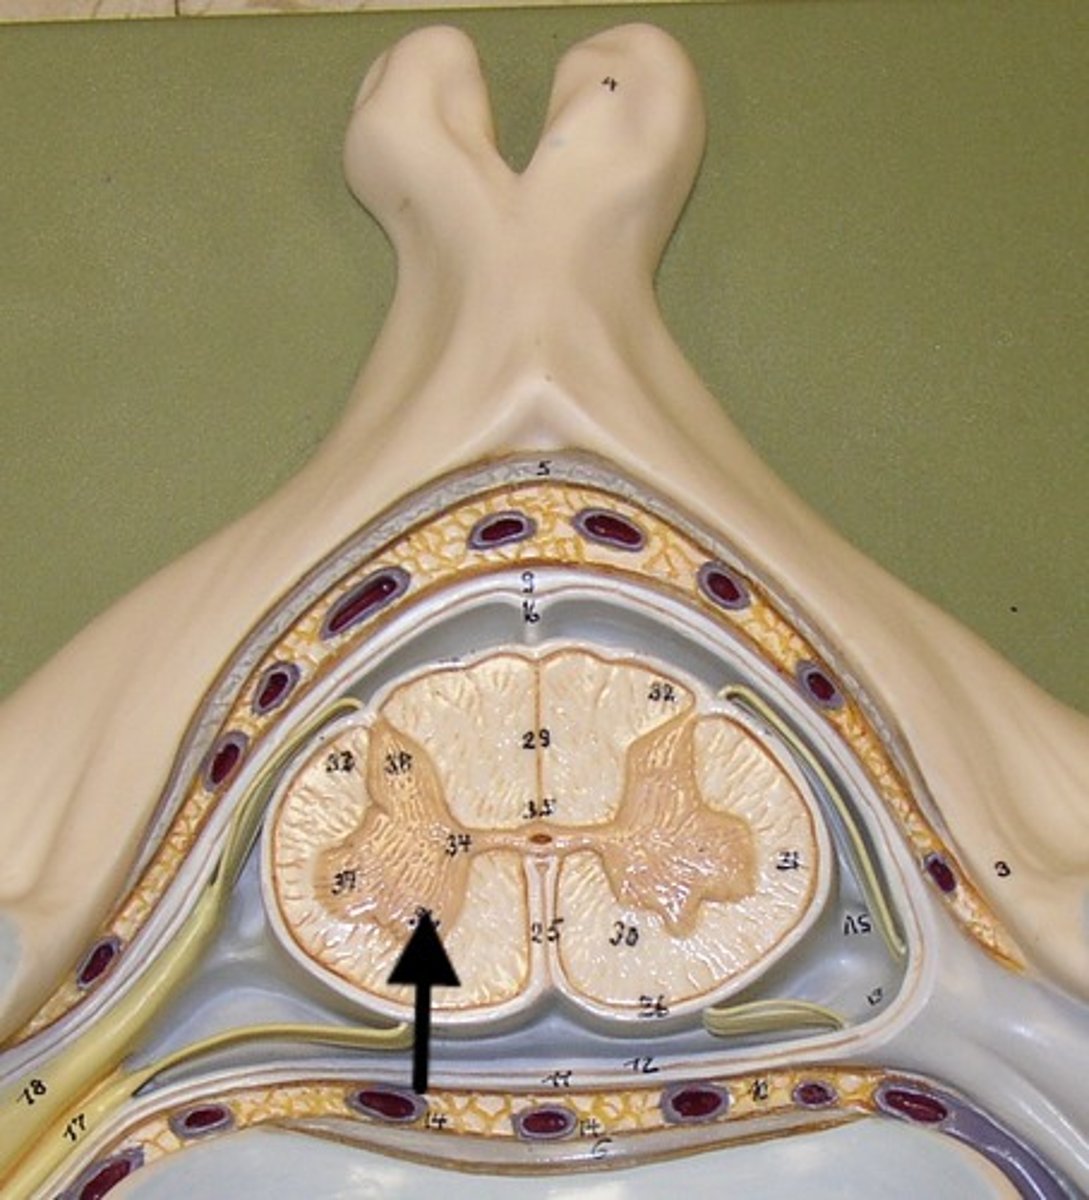

subarachnoid space anatomy

gray mater spinal